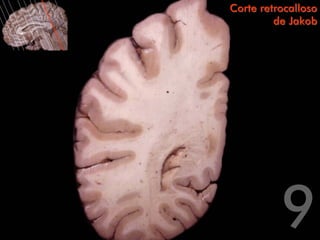

Corte retrocalloso

de Jakob

Centro oval del lóbulo

parietal

Surco del cíngulo

Asta occipital del ventrículo            Circunvolución del

lateral                                  cíngulo

Circunvolución

temporal superior                    Bulbo del asta

occipital

Tapetum

Fórceps mayor

Radiación óptica

Calcar avis

Fascículo longitudinal

inferior                         Surco calcarino

temporal media

Circunvolución                   Eminencia colateral

occipitotemporal lateral

Corte retrocalloso de Jakob Centro oval del lóbulo parietal Surco del cíngulo Asta occipital del ventrículo Circunvolución del lateral cíngulo Circunvolución temporal superior Bulbo del asta occipital Tapetum Fórceps mayor Radiación óptica Calcar avis Fascículo longitudinal inferior Surco calcarino Circunvolución temporal media Circunvolución Eminencia colateral occipitotemporal lateral